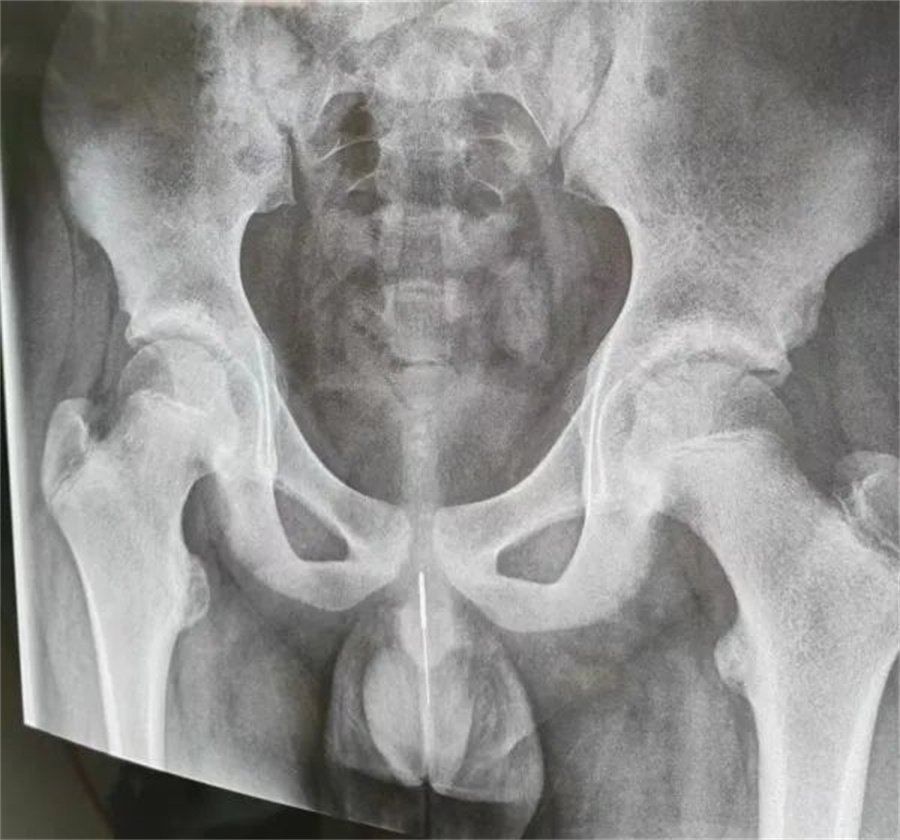

“孩子大概是中午的时候把银针塞进尿道中,因为针灸银针前段柔软纤细而末段又有增粗的螺旋状柄头,所以很难取出来。家长已经带他在当地医院拍片确诊,晚上7点多转到我们医院,当时孩子尿道口有血,疼痛难忍......”a片网站

急诊外科接诊后立即收入院并第一时间做好手术准备,此时泌尿外科主任谢方达也紧急从家中赶到了医院,经过术前检查,确认银针卡在了接近球部尿道的部位,位置比较深,又没进入到膀胱里,如何尽快地取针成为一个颇具难度的挑战。

孩子家长和泌尿外科专家都希望用最微创的方式完成手术。但因孩子年龄小、尿道细,体重又偏大而难以实现,术中医生在保证对孩子造成伤害最小的前提下,采取隐匿小切口的方式,顺利将6.5cm的银针从尿道中刺破取出,为孩子解除了困扰,术后恢复三四天后即可顺利出院。